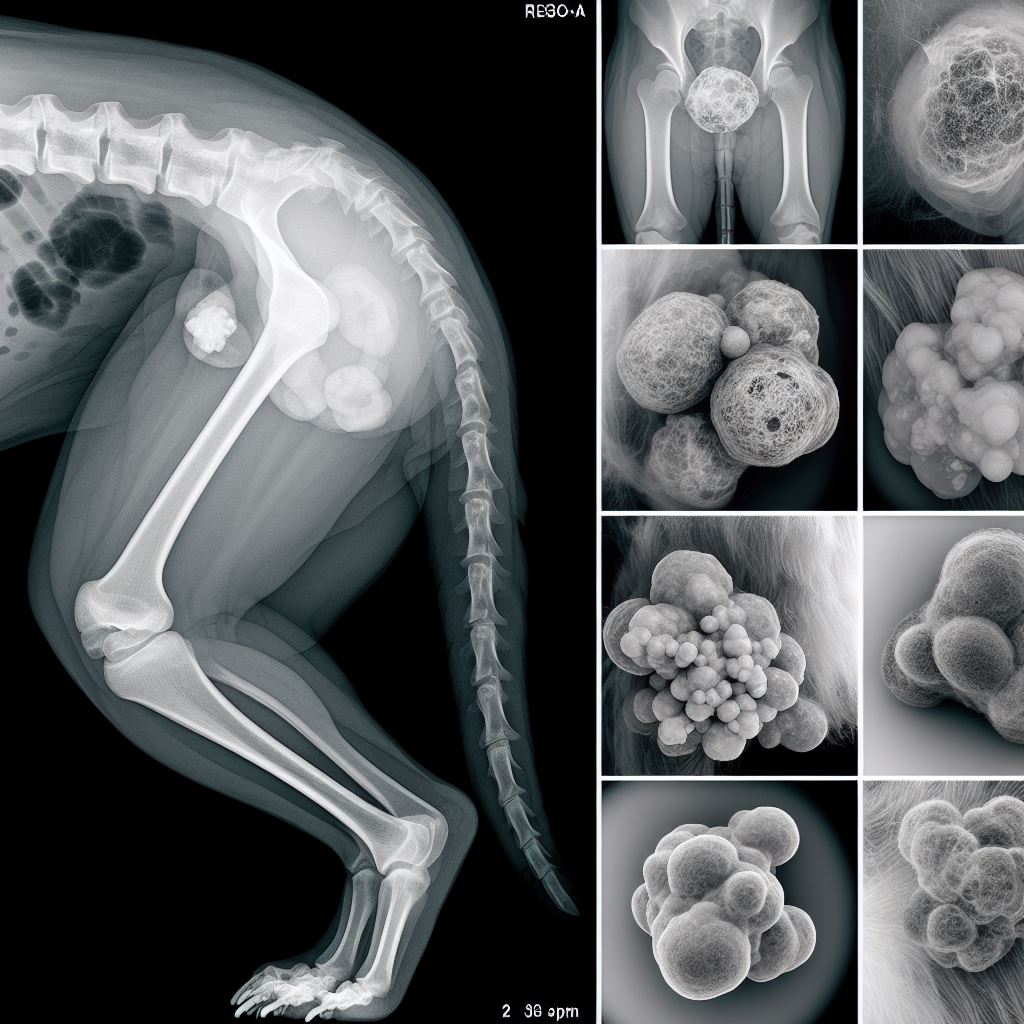

강아지 지방종은 지방 세포에서 비롯된 종양으로, 부드럽고 이동 가능한 덩어리 형태로 나타납니다. 종양 내부에는 지방이 축적되어 부풀어 오르는 특징이 있습니다. 이러한 종양은 주로 표면에 덩어리 형태로 나타나며, 부드럽고 움직이기 쉽습니다. 종양이 자라면서 피부 위로 돌출되는 것이 일반적입니다.

강아지 지방종은 종양으로써, 주로 강아지의 피부에 나타납니다. 이 종양은 표면에 덩어리 형태로 형성되며, 부드럽고 움직이기 쉽습니다. 종양이 자라면서 피부 위로 돌출되는 것이 일반적입니다. 종종 털로 덮여있는 부위에서 발견되며, 크기와 수는 다양할 수 있습니다. 색깔은 주로 피부색과 비슷하거나 다소 어두울 수 있습니다. 강아지 지방종이 나타나는 증상은 종양의 크기와 위치에 따라 다를 수 있습니다. 작은 종양이라면 주변 피부에 거의 눈에 띄지 않을 수도 있지만, 크거나 빠르게 성장하는 종양은 피부 위로 돌출되어 뚜렷하게 보일 수 있습니다. 종양이 자라면서 강아지는 종종 가려움증이나 통증을 경험할 수도 있습니다. 종양이 부딪히거나 마찰을 받을 경우 출혈이나 염증이 발생할 수도 있습니다.

지방종과 유사한 피부 종양은 강아지의 건강에 영향을 줄 수 있는 다른 질병들에 의해 유발될 수 있습니다. 예를 들어, 여드름, 낭종, 피부염 등의 질병이 지방종과 유사한 증상을 보일 수 있습니다. 이러한 경우, 정확한 진단을 위해 수의사의 도움이 필요합니다. 수의사는 증상을 평가하고 필요한 검사를 시행하여 진단을 정확히 내릴 수 있습니다. 예를 들어, 피부 조직 검사나 조직 생검을 통해 종양의 성격을 확인할 수 있습니다. 강아지의 피부 종양이 지방종인지 다른 질병인지 정확히 알기 위해서는 전문가의 도움이 필요합니다. 피부 종양의 모양, 크기, 피부의 색깔 등을 자세히 관찰하고, 강아지의 증상과 함께 수의사에게 상담을 받는 것이 중요합니다.

강아지 지방종은 지방 세포에서 비롯된 종양으로, 대부분의 경우 무해합니다. 이것은 부드럽고 이동 가능한 덩어리 형태로 나타나며, 종종 피부 위로 돌출되는 것이 특징입니다. 지방종은 특별한 증상을 보이지 않는 경우가 많지만, 가끔 가려움증이나 통증을 경험할 수도 있습니다. 수의사의 도움을 받아 정확한 진단을 받고, 적절한 치료 방법을 선택하는 것이 중요합니다. 감시 대기, 약물 치료, 수술적 제거, 방사선 치료 등 다양한 치료 방법이 있으니 수의사와 상의하여 최적의 방법을 선택해야 합니다.